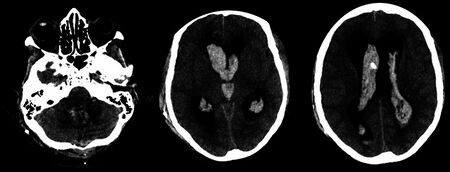

Factor XI deficiency-CT scans showing hemorrhagic congestion of choroid plexus (lab results indicated a partial deficiency of FXI where 34 IU/dl was found versus normal range 70–120 IU/dl)

The diagnosis of haemophilia C (factor XI deficiency) is centered on prolonged activated partial thromboplastin time (aPTT).One will find that the factor XI has decreased in the individuals body. In terms of differential diagnosis one must consider: haemophilia A, haemophilia B, lupus anticoagulant and heparin contamination.[4][9] The prolongation of the activated partial thromboplastin time should completely correct with a 1:1 mixing study with normal plasma if haemophilia C is present; in contrast, if a lupus anticoagulant is present as the cause of a prolonged aPTT, the aPTT will not correct with a 1:1 mixing study.[citation needed]